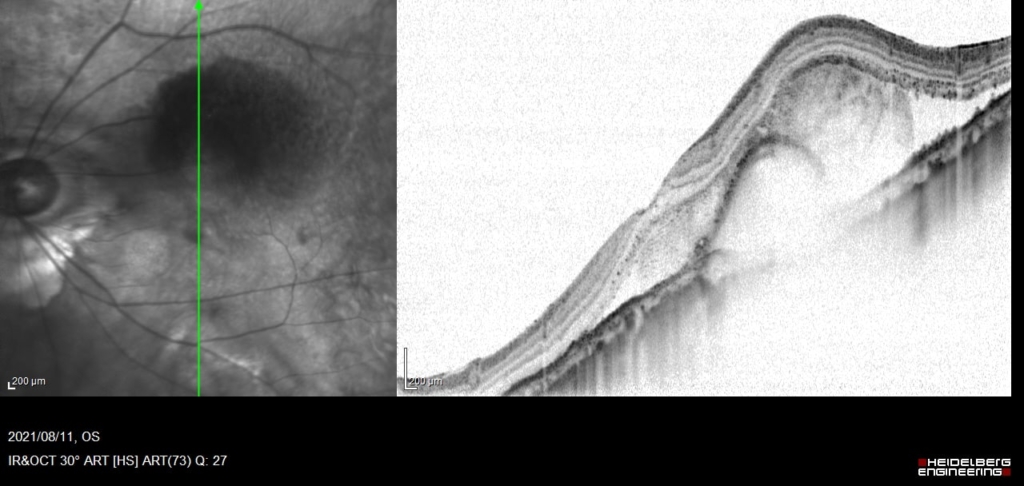

初診時

網膜下出血と出血性PEDがみられる。

低いPEDの内部は中等度~低反射が混在しており新生血管と考えられる。